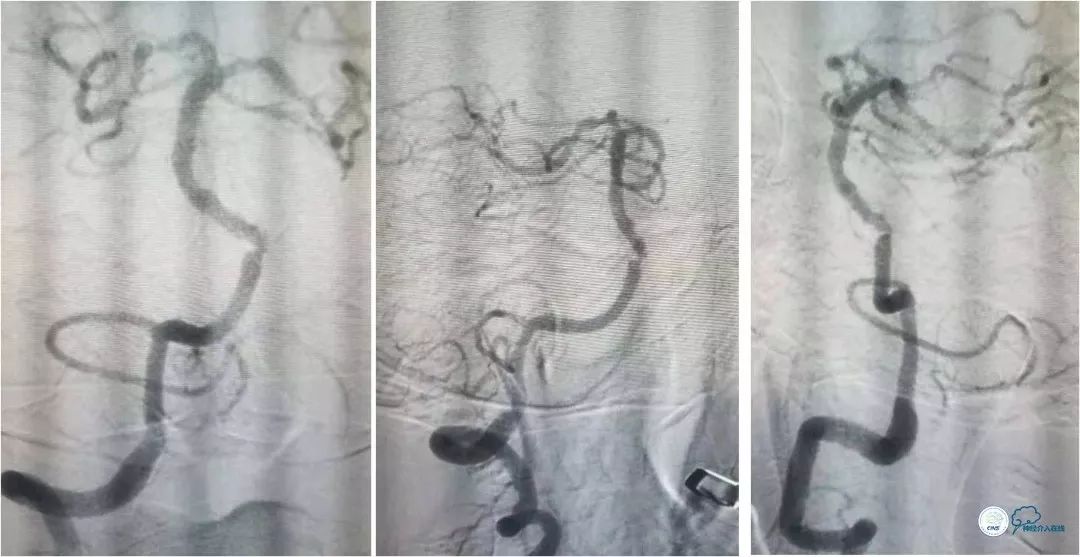

全麻下右侧股动脉穿刺置入6F动脉鞘, 6F导引导管至左椎动脉V2段远端,术前造影示左椎动脉V4段与基底动脉交界处重度狭窄(图8)。

图8

路径图下经交换技术送入Transend微导丝(0.014″,300cm)至左大脑后动脉。沿微导丝送入Gateway球囊(2.25mm×9mm)于狭窄处预扩张,扩张后造影提示狭窄程度明显改善(图9)。

图9